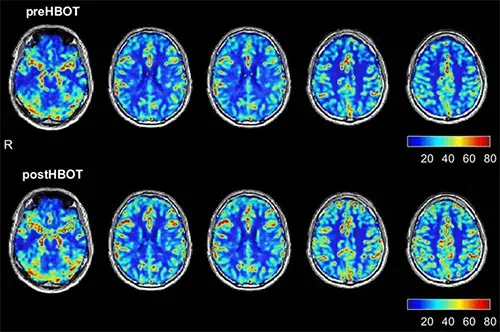

In our clinic at AMA Regenerative Medicine & Skincare we have seen this first hand. Many patients report that their neurological issues, the headaches and the throbbing migraines and the pounding cluster headaches begin to feel relieved even after their first treatment in the hyperbaric chamber.